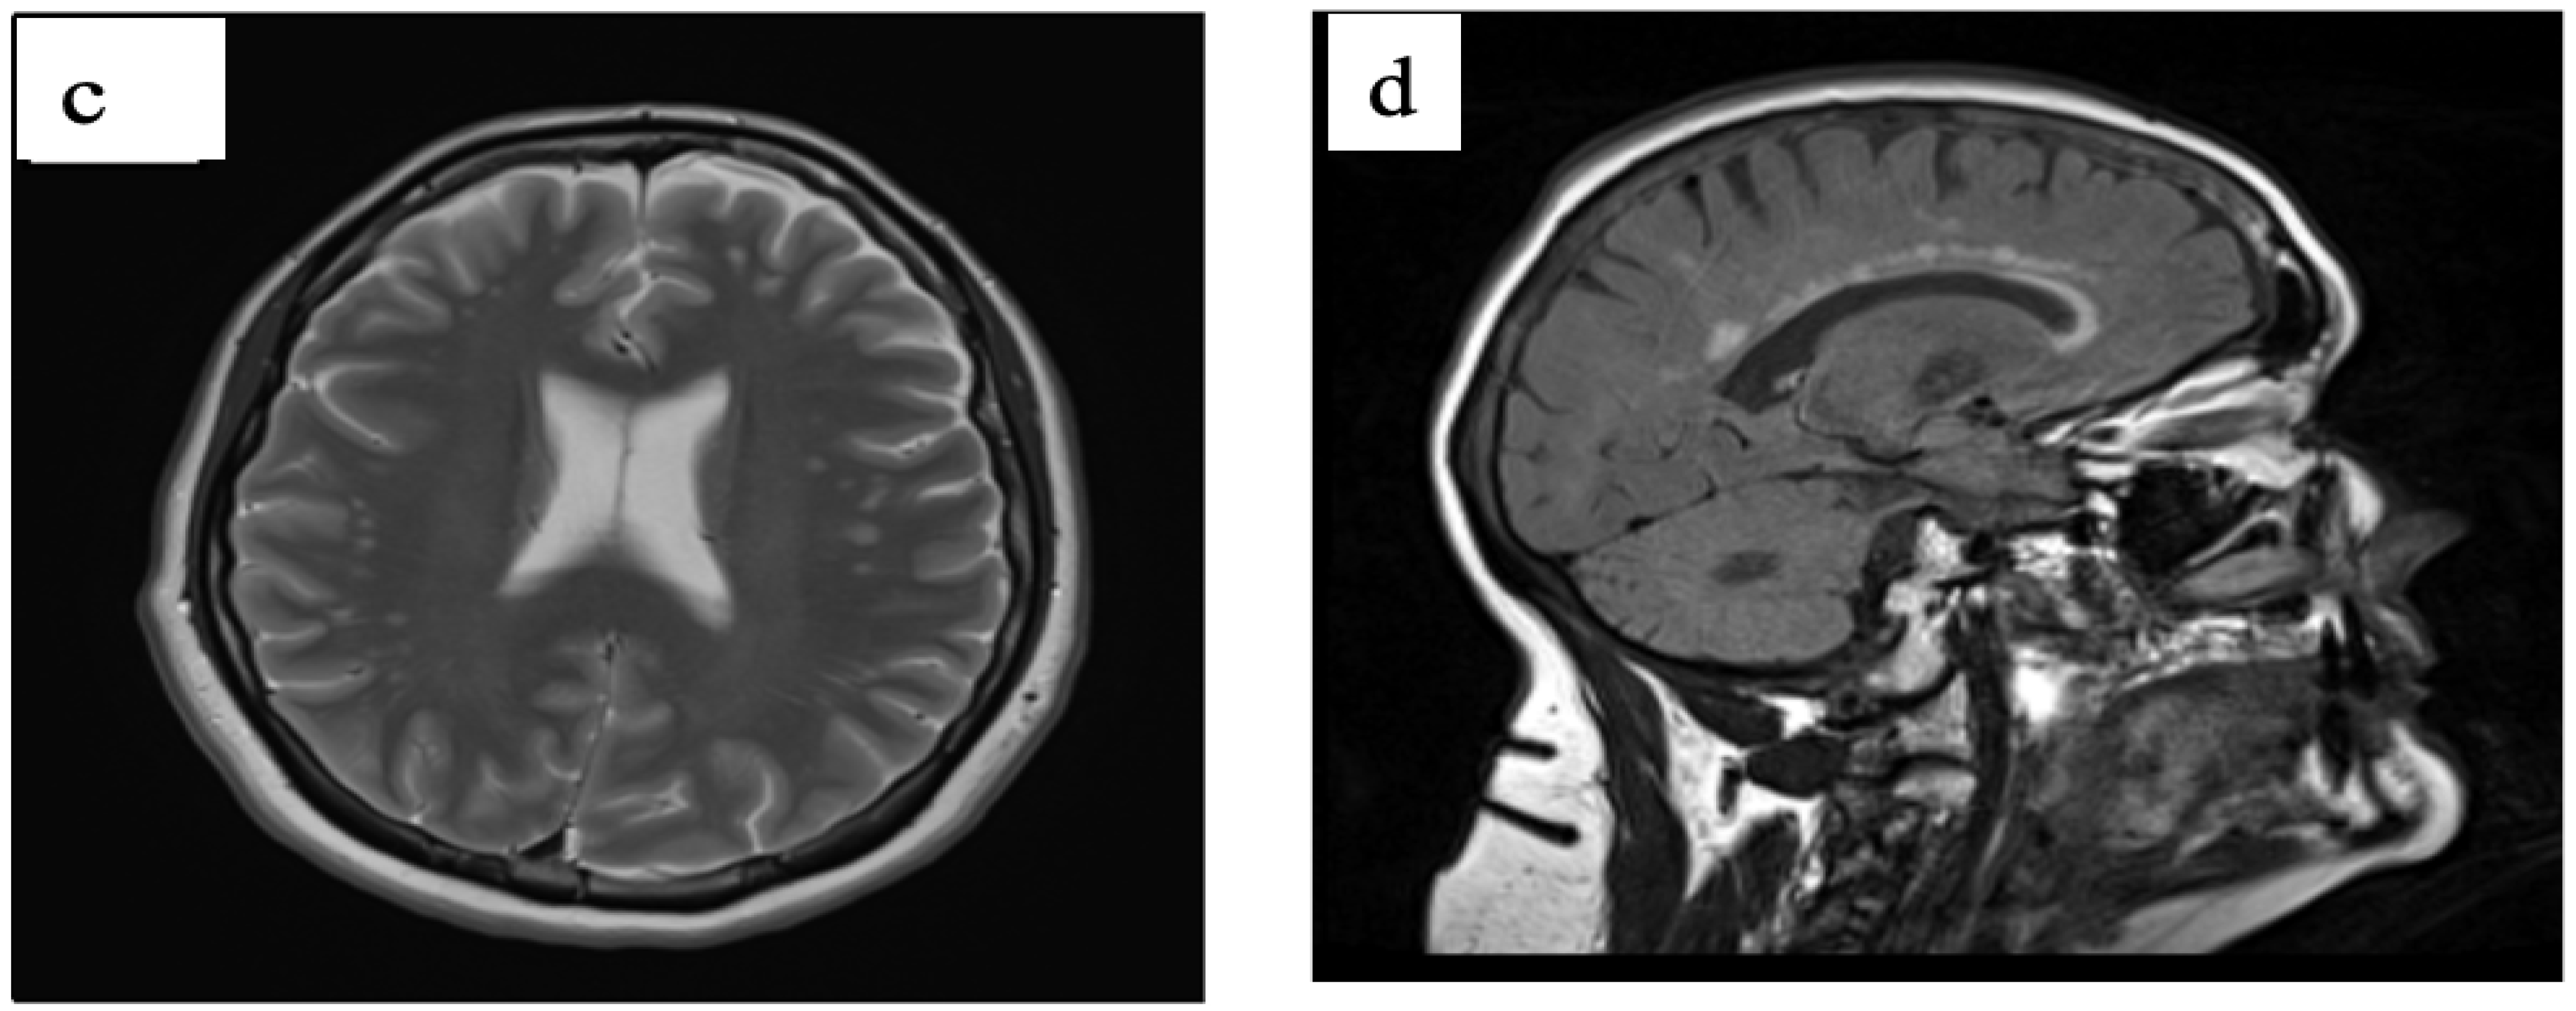

3.3. Case 3

3.4. Case 4